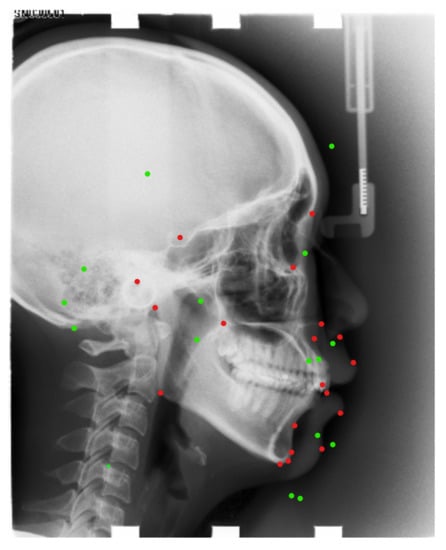

Figure 8 shows one of the examples of our results.

Figure 8. Green points: predicted landmarks’ locations. Red points: ground-truth of landmarks’ locations.